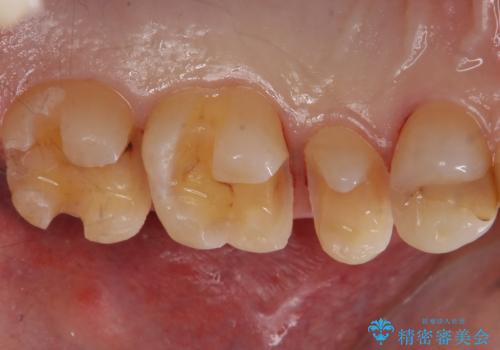

虫歯を取りつつ銀歯を外し、セラミックインレーでの修復処置を行います。

処置中に手前の歯の詰め物の不適合が確認されたため、追加で治療していくこととなりました。

銀の詰め物と不適合な詰め物を精度の良いセラミックインレーに変えることができました。